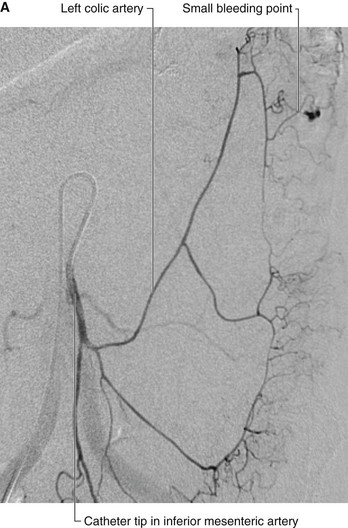

Renal cell tumors are unusual because not only do they grow outward from the kidney, invading the fat and fascia, but they also spread into the renal vein. This venous extension is rare for any other type of tumor, so, when seen, renal cell carcinoma should be suspected. In addition, the tumor may spread along the renal vein and into the inferior vena cava, and in rare cases can grow into the right atrium across the tricuspid valve and into the pulmonary artery (Figs. 4.142 and 4.143).

image

Fig. 4.142 Tumor in the right kidney growing toward, and possibly invading, the duodenum. Computed tomogram in the axial plane.

Fig. 4.143 Tumor in the right kidney spreading into the right renal vein. Computed tomogram in the axial plane.

Treatment for most renal cancers is surgical removal, even when metastatic spread is present, because some patients show regression of metastases.